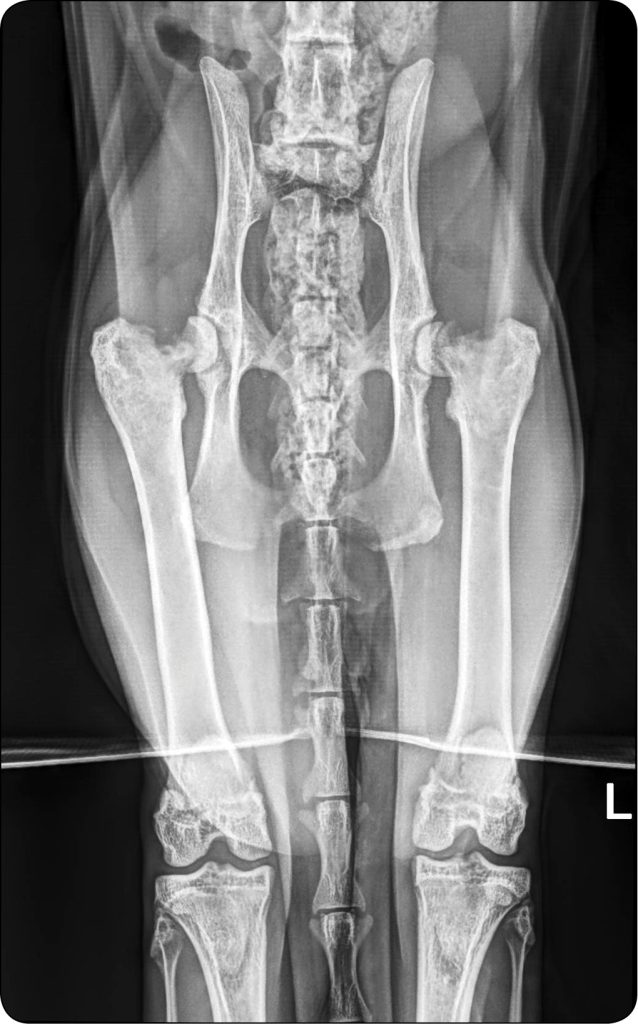

Kot, maine coon, samiec, 18 miesięcy, waga: 9 kg, kastrowany w wieku 5 miesięcy. Trafił do przychodni z powodu przewlekłej, trwającej od kilku miesięcy kulawizny prawej kończyny miednicznej, która uległa pogorszeniu w przeciągu ostatnich 2 tygodni. Brak notowanego urazu. Podczas wizyty w gabinecie zaobserwowano kulawiznę 3. stopnia – przemijającą, bez obciążania kończyny. W badaniu klinicznym wykazano znaczne ograniczenie ruchu w prawej kończynie miednicznej, bolesność i krepitację podczas manipulacji. Wykonano badanie RTG w pozycji wentralno-dorsalnej z wyprostowanymi kończynami, które ukazało zmiany lityczne w obrębie szyjki głowy kości udowej w obu kończynach miednicznych. W prawej kończynie miednicznej zmiany radiologiczne były silniej wyrażone, dając podejrzenie całkowitego odseparowania głowy od szyjki kości udowej. Ze względu na występujące czynniki ryzyka (wiek, płeć, masa, wczesna kastracja) objawy kliniczne oraz wynik badania klinicznego i radiologicznego postawiono diagnozę osteopatii przynasadowej i zdecydowano o obustronnej operacji resekcji głowy i szyjki kości udowej. Zalecono miesięczną przerwę pomiędzy zabiegami w celu regeneracji oraz fizjoterapii mającej za zadanie zwiększenie masy mięśniowej pierwszej operowanej kończyny. Śródoperacyjnie stwierdzono całkowite odseparowanie nasady głowy kości udowej od przynasady.